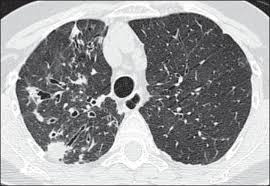

Lady windermere syndrome treatment. Complex or MAC which are present in soil and water. Treatment with thoracoscopic lobectomysegmentectomy for right middle lobe and lingular bronchiectasis associated with non-tuberculous mycobacterial disease. This case illustrates the classic chest radiograph and computed tomography findings of The Lady Windermere Syndrome.

Eur J Cardiothorac Surg 40 2011 pp. A lady as described in literature is a woman of good social standing and has a polite and refined disposition. The radiographic findings are bronchiectasis and small nodules predominately located within the middle lobe and lingula. These organisms enter hosts via the gastrointestinal tract or the lungs. Lady Windermere syndrome Ann Marie Kumfer MD Hawa Edriss MD AbstrAct Non-tuberculosis Mycobacterium spp NTM pulmonary disease is increasing in incidence and is a common cause of undiagnosed lung disease in older patients. Dr Surya Bhatt 801 Ostrum Street Bethlehem Pennsylvania USA 18015 Tel. Treatment with thoracoscopic lobectomysegmentectomy for right middle lobe and lingular bronchiectasis associated with non-tuberculous mycobacterial disease. Lady Windermeres Syndrome In 1992 two physicians published a medical article describing six older women with infection of their lungs by the germ Mycobacterium avium. The Lady Windermere syndrome.